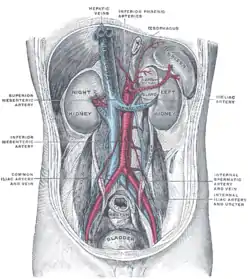

Any obstruction of the venous vasculature of the liver is referred to as Budd–Chiari syndrome, from the venules to the right atrium. This leads to increased portal vein and hepatic sinusoid pressures as the blood flow stagnates. The increased portal pressure causes increased filtration of vascular fluid with the formation of ascites in the abdomen and collateral venous flow through alternative veins leading to esophageal, gastric and rectal varices. Obstruction also causes centrilobular necrosis and peripheral lobule fatty change due to ischemia. If this condition persists chronically what is known as nutmeg liver will develop. Kidney failure may occur, perhaps due to the body sensing an "underfill" state and subsequent activation of the renin-angiotensin pathways and excess sodium retention.[15]